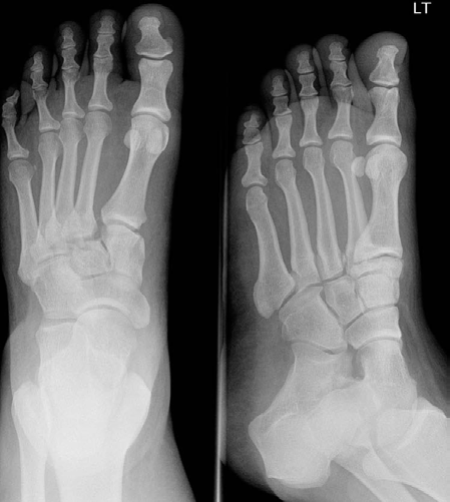

EXAMINER : A 49-year-old lady fell on the stairs. Her foot is very painful, bruised, swollen and she can’t bear weight. The CT1 went to see her in A&E, but he is not sure what the problem is, what do you think? (Figure 8.3.) CANDIDATE : AP and oblique radiographs of left foot. There is diastasis of > 2 mm between the base of the first and second metatarsals, features suggestive of Lisfranc tarsometatarsal fracture dislocation. There is a small avulsed fragment of bone in that interval. This avulsion fracture could be from the insertion of the Lisfranc ligament into the base of the second metatarsal, called a ‘fleck sign’. [Always ask for the lateral radiograph.] EXAMINER : Okay, how will you manage this patient? CANDIDATE : I would start with assessing the patient as a whole, following ATLS protocol. I would take relevant history: mechanism of injury, patient’s general condition, past medical history, allergies, smoking as well as occupation and previous level of activity.

Figure 8.3 Anteroposterior (AP) and oblique radiographs left foot.